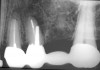

Although there have been trends to use prefabricated post systems, there are specific clinical situations where a morphological, custom-cast post-and-core with a high-noble alloy would be beneficial. A cast post-and-core is the restoration of choice for clinical circumstances where there is limited tooth structure available to develop a ferrule when preparing the tooth for a crown or when there is insufficient tooth structure available to create an anti-rotational design to the core on a prefabricated post.6 Mandibular incisors, maxillary incisors, and canines that have minimal amounts of coronal tooth structure remaining are good candidates for a custom, morphological cast-gold post and core.4-6,69 There are two techniques that can be used when fabricating a custom-made, laboratory-fabricated post. A custom-made post can be fabricated directly in the mouth on the tooth preparation using a plastic post that is burnt-out during the metal-casting or ceramic-pressing process. A more predictable technique uses an impression of the tooth preparation and the root canal (Figure 9A and Figure 9B). This saves chairtime. The impression is poured by the laboratory and casting patterns are made on the master cast by the laboratory technician for casting in either metal or ceramic (Figure 10). The final custom-made post is then cemented into the root canal (Figure 11).

Figure 9a  Maxillary incisors (with short roots) after endodontic treatment, crown margin, and post preparation.

Figure 9a

Figure 9b  Impression of the crown and root canal post preparation.

Figure 9b